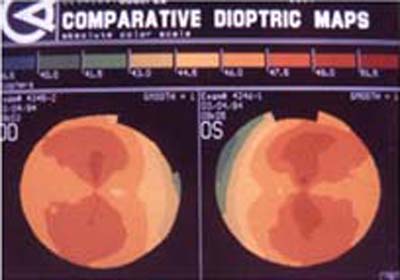

Con esta metodología, los poderes altos de la superficie corneal son representados en colores cálidos como el amarillo, naranja y rojo (Foto 2) mientras que las áreas de bajo poder se las representa en colores más frios como el verde y el azul. ( Foto 3), facilitandose así visualización de los efectos de la cirugía refractiva y la comprensión de sus resultados ( Foto 4 y 5)